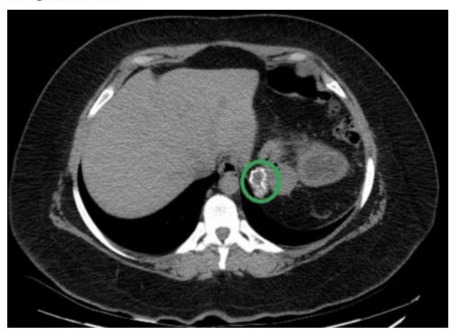

A 22-year-old female patient was admitted to the emergency room on November 8, 2023 due to pain in the left hypochondrium, fever of 39°C, and wet cough. The condition began on September 13 with pain in the right scapular area that radiated to the left hypochondrium. She was initially treated with analgesics and antibiotics without improvement. The initial ultrasound was inconclusive, so an abdominal computed tomography (CT) scan was performed, which revealed a complex cystic lesion dependent on the spleen measuring 240x171x190 mm, with smooth edges and some calcifications. Loss of the usual morphology of the spleen and displacement of adjacent structures were observed, accompanied by left laminar pleural effusion. CA 19-9 levels were 25.5 U/mL. The initial diagnosis was a giant splenic cyst. During the preoperative evaluation, the patient was classified as having ASA III anesthetic risk. Preoperative examinations showed anemia (Hb: 9.6 g/dL) and coagulation disorders (INR: 1.57), so she was given a preoperative transfusion of packed red blood cells and fresh frozen plasma to correct the anemia and coagulation disorders. An exploratory laparotomy was scheduled for November 14, a procedure that lasted approximately 4 hours and revealed the following findings: (1) a giant 40x30 cm splenic cyst with greenish contents, (2) firm adhesions to the tail of the pancreas, stomach, colon, and omentum, (3) an ovarian cyst, and (4) no visible or palpable liver lesions.

Figure 2: The initial ultrasound was inconclusive, so an abdominal tomography (CT) was performed, which revealed a complex cystic lesion dependent on the spleen measuring 240x171x190 with smooth edges and some calcifications

The presented case of a giant splenic cyst in a young patient offers an opportunity to discuss important aspects of the diagnosis, management and follow-up of this rare condition. The clinical presentation of this case, with abdominal pain, fever, and cough, is consistent with the existing literature on giant splenic cysts. According to Ingle et al. (2014), the most common symptoms include left upper quadrant pain, nausea, and vomiting, which are attributed to the mass effect of the cyst [9]. However, the initial presentation with left shoulder pain is an interesting finding that could be attributed to diaphragmatic irritation, a phenomenon described by Farhangi et al. (2016) in cases of large splenic cysts [10]. The use of an ultrasound followed by a CT scan for diagnosis follows the approach recommended by Geraghty et al. (2009) [11]. The CT scan not only confirmed the presence of the cyst, but it also provided crucial information about its size (240x171x190 mm) and anatomical relationships, essential for surgical planning.